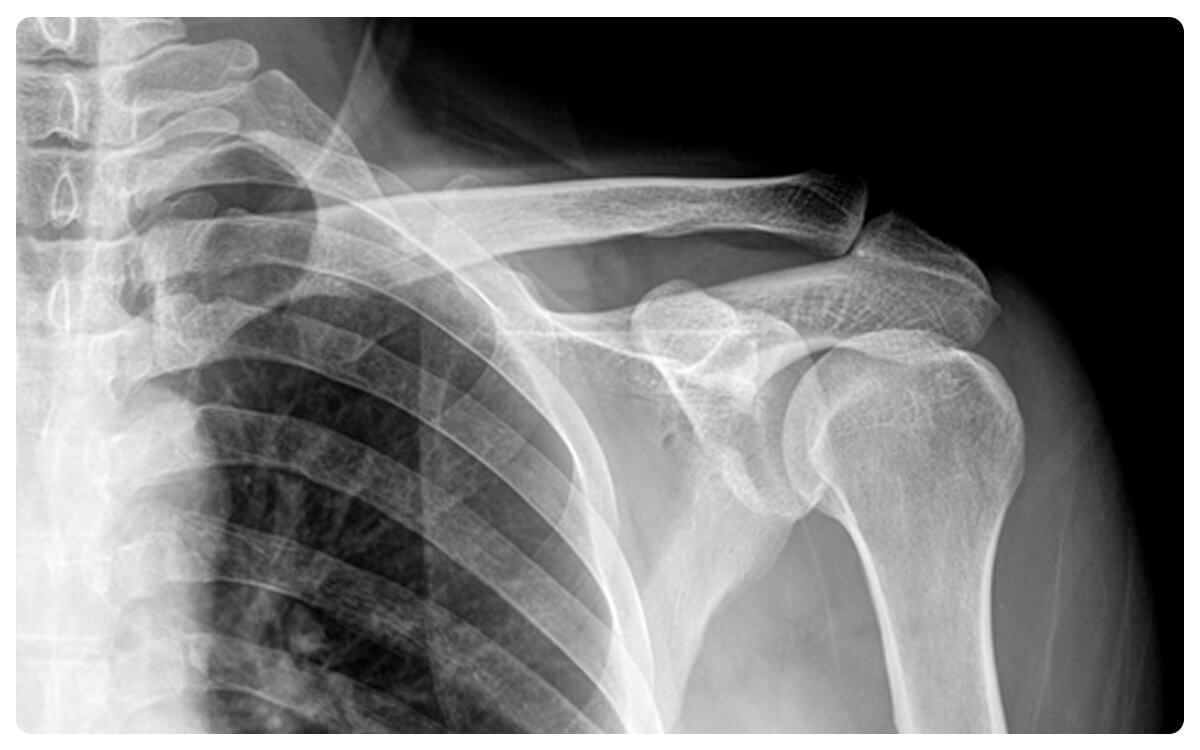

La Radiografía de Hombros en Proyección Anteroposterior (AP) se establece como una herramienta esencial en la radiología diagnóstica, brindando una visión detallada y estructurada de la anatomía y posibles afecciones de la región del hombro.

A través de la emisión controlada de radiación, esta técnica no invasiva proporciona imágenes bidimensionales que permiten la evaluación de los huesos de la articulación del hombro y sus estructuras circundantes desde una perspectiva frontal.

La Radiografía de Hombros en Proyección AP desempeña un papel crucial en la detección y diagnóstico de fracturas, desplazamientos, desgaste articular y otras patologías que afectan esta área, proporcionando información valiosa para la toma de decisiones clínicas informadas y el manejo adecuado de las afecciones relacionadas con los hombros.